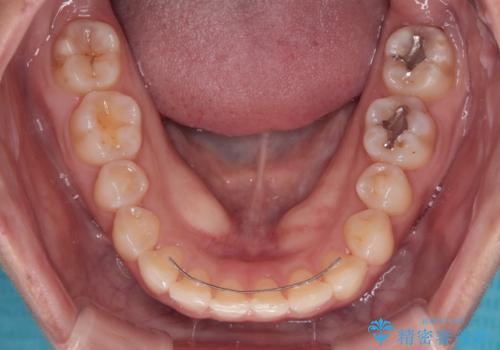

- クリアブラケット

- 1年7ヶ月

舌の突出癖により上下前歯が開咬となりましたが、舌のトレーニングと顎間ゴムの使用により、元々の被蓋関係に改善することができました。

アンカースクリューを用いて、出っ歯仕上がりを回避し、正中位置も改善することができました。